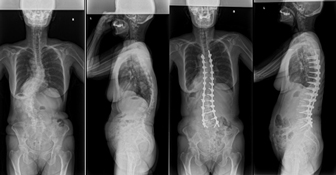

前方矯正固定術

わき腹やおなかを切開してチタンなどで作られた椎体スクリューを背骨に挿入して、ロッドと呼ばれる金属のバーで固定して、せぼねの矯正と固定を行います。術後胸に胸腔ドレーンと呼ばれるドレーンを数日入れる場合があります。手術部の安静を保つために装具を3-6ヶ月程度着用します。

大人の患者様では3週間程度で場合によってはリハビリテーション病院へ転院をして頂き、さらにリハビリテーションを行います。

入院は小児患者様で2週間程度、大人の患者様では2週間程度で場合によってはリハビリテーション病院へ転院をしていただき、さらにリハビリテーションを行います。